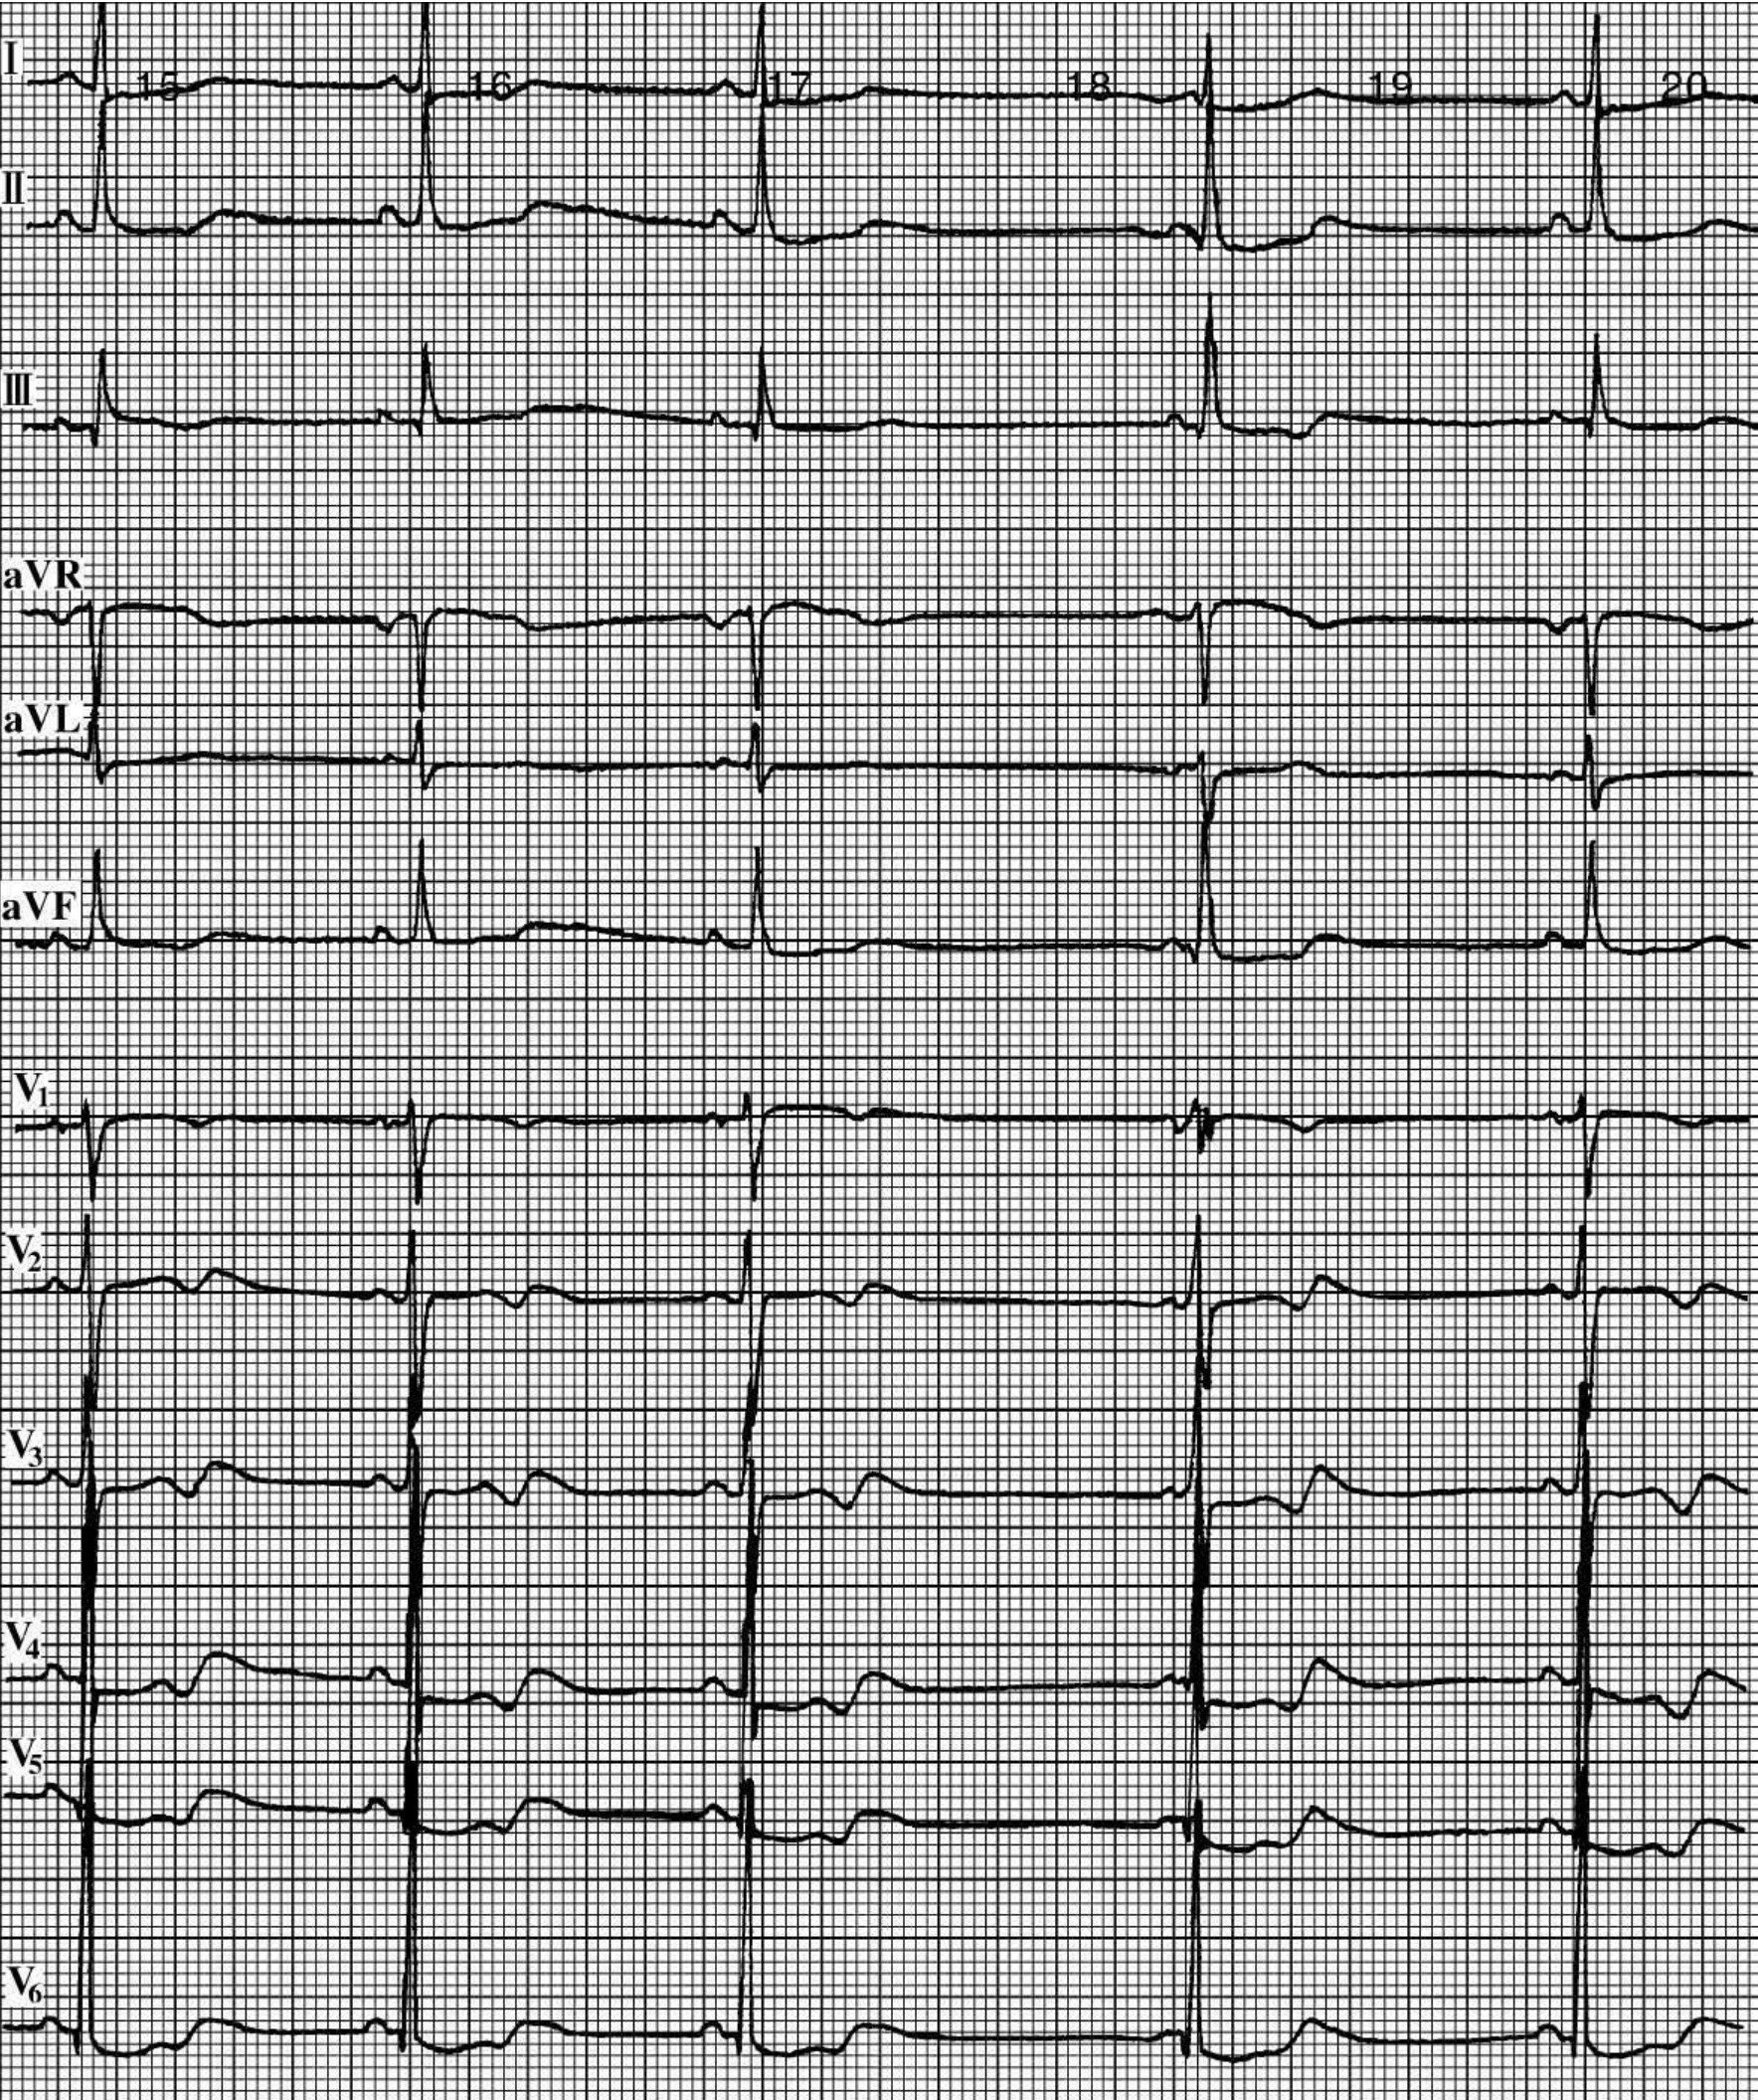

img293

图17-5 多发性肌炎心电图

女性,68岁,多发性肌炎。窦性心律,肢导QRS低电压,右束支传导阻滞,V1~V5导联ST段下降,T波倒置及双向,Q-T间期0.45s